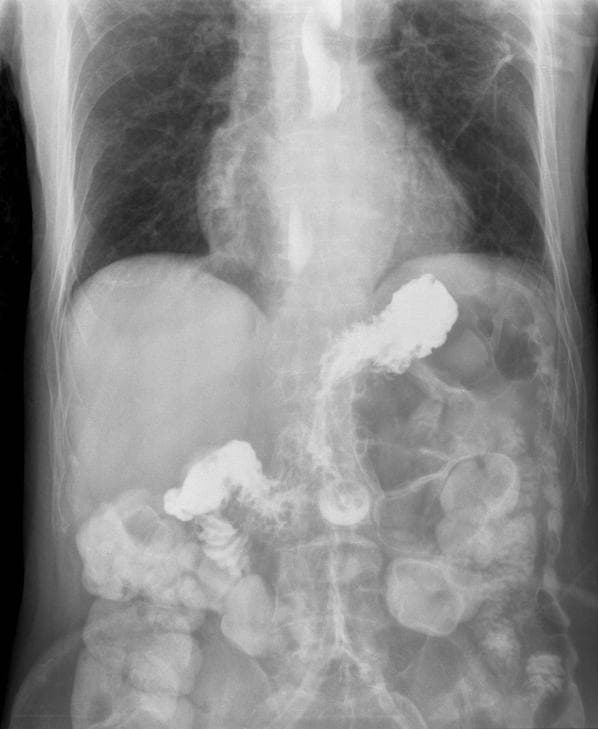

Matinding sakit sa mga parte ng katawan na. Napansin na namin na parang hindi nawawala ang ubo ni bunso bagamat hindi naman malala ang pag-ubo niya. Ayon kay Guiang kadalasang nasusuri ang mga sakit sa baga sa pamamagitan ng chest x-ray lalo na kung malubha ito.

Dito na kasi aniya nakikita ang mga senyales ng mga malulubhang sakit gaya ng mga bukol o tubig sa baga at iba pa. Ang pangunahing pag-iwas ay ang pagtigil sa paninigarilyo at pagkain ng tama. Lung water lung tumor lung cancer tubig sa baga lung symptoms.